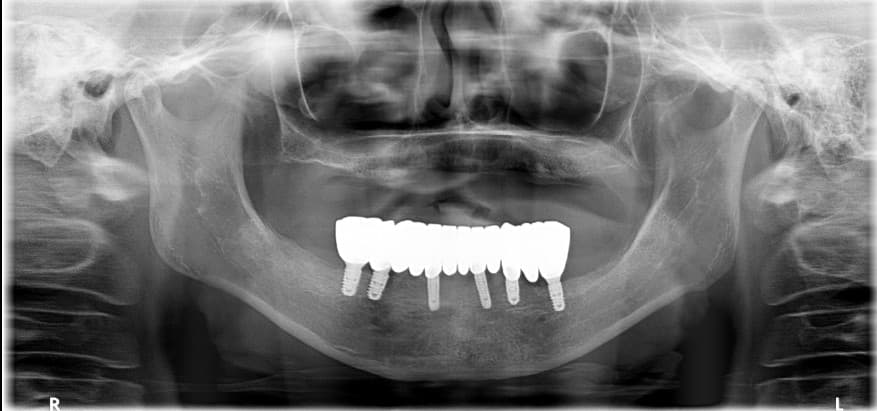

Park●● · 70 yoshdan oshgan erkak

Pastki jag to'liq implant

To'liq implant uchun nechta implant kerak?

Odatda yuqori jag' (yuqori tishlar) uchun 6 ta, pastki jag' (pastki tishlar) uchun 4 ta asosiy hisoblanadi. Lekin bemorning milka suyagi holatiga qarab o'zgarishi mumkin, Yonsei Ona Stomatologiyasi minimal implant bilan maksimal samaraga erishadigan loyiha tuzadi. 3D CT aniq diagnostikasidan keyin optimal son ma'lum qilinadi.